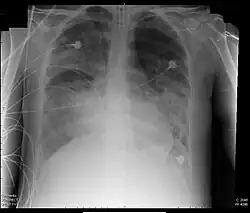

Diffuse Lungeninfiltrate im Röntgenbild

2. Radiologie: Beidseitige Infiltrate im Röntgenbild der Lunge oder in der Computertomographie ohne andere sinnvolle Erklärung,

• diffuse röntgenologische Infiltration